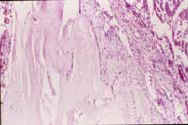

Paciente de 17 años, sexo femenino, que consulta en junio de 1997 por deformidad en hombro derecho de un año de evolución, sin manifestaciones clínicas; radiológicamente se encontró reabsorción parcial del extremo distal de la clavícula, en “punta de lápiz”. El reporte de la biopsia señaló tejido fibroblástico con proliferación angiomatosa de apariencia benigna compatible con osteolisis masiva (enfermedad de Gorham) (Figura 4).

Figura 4. Microfotografía de lámina histología en HE, con aumento x 200.